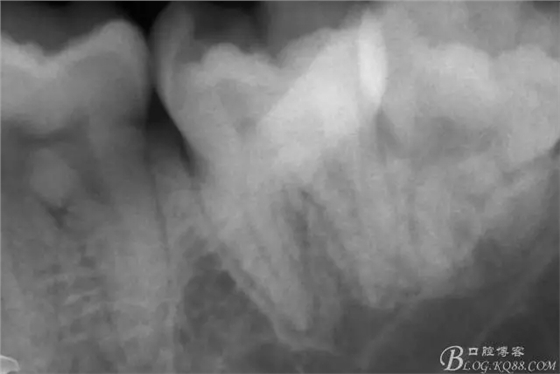

第二次復(fù)診,37叩(+-)。去除暫封物,沖洗,8號~12號挫疏通根管,15號挫用VDW電測確定根管工作長度,M :18mm D :18mm,對應(yīng)洞緣為標記點。其中近中根管感覺是頰舌兩根管,但進針感覺又是一根管,運用Crown Down Technique預(yù)備法,M3挫登士柏機動配合EDTA,1%次氯酸鈉,生理鹽水交替沖洗。紙尖干燥,封氫氧化鈣。

一周后復(fù)診,37叩(—)。去除暫封物,沖洗,試主尖拍片。

X線示牙膠尖到達工作長度,故行AH-PLUSH糊劑配合卡瓦熱牙膠機運用連續(xù)波充法根充,暫封拍根尖片。